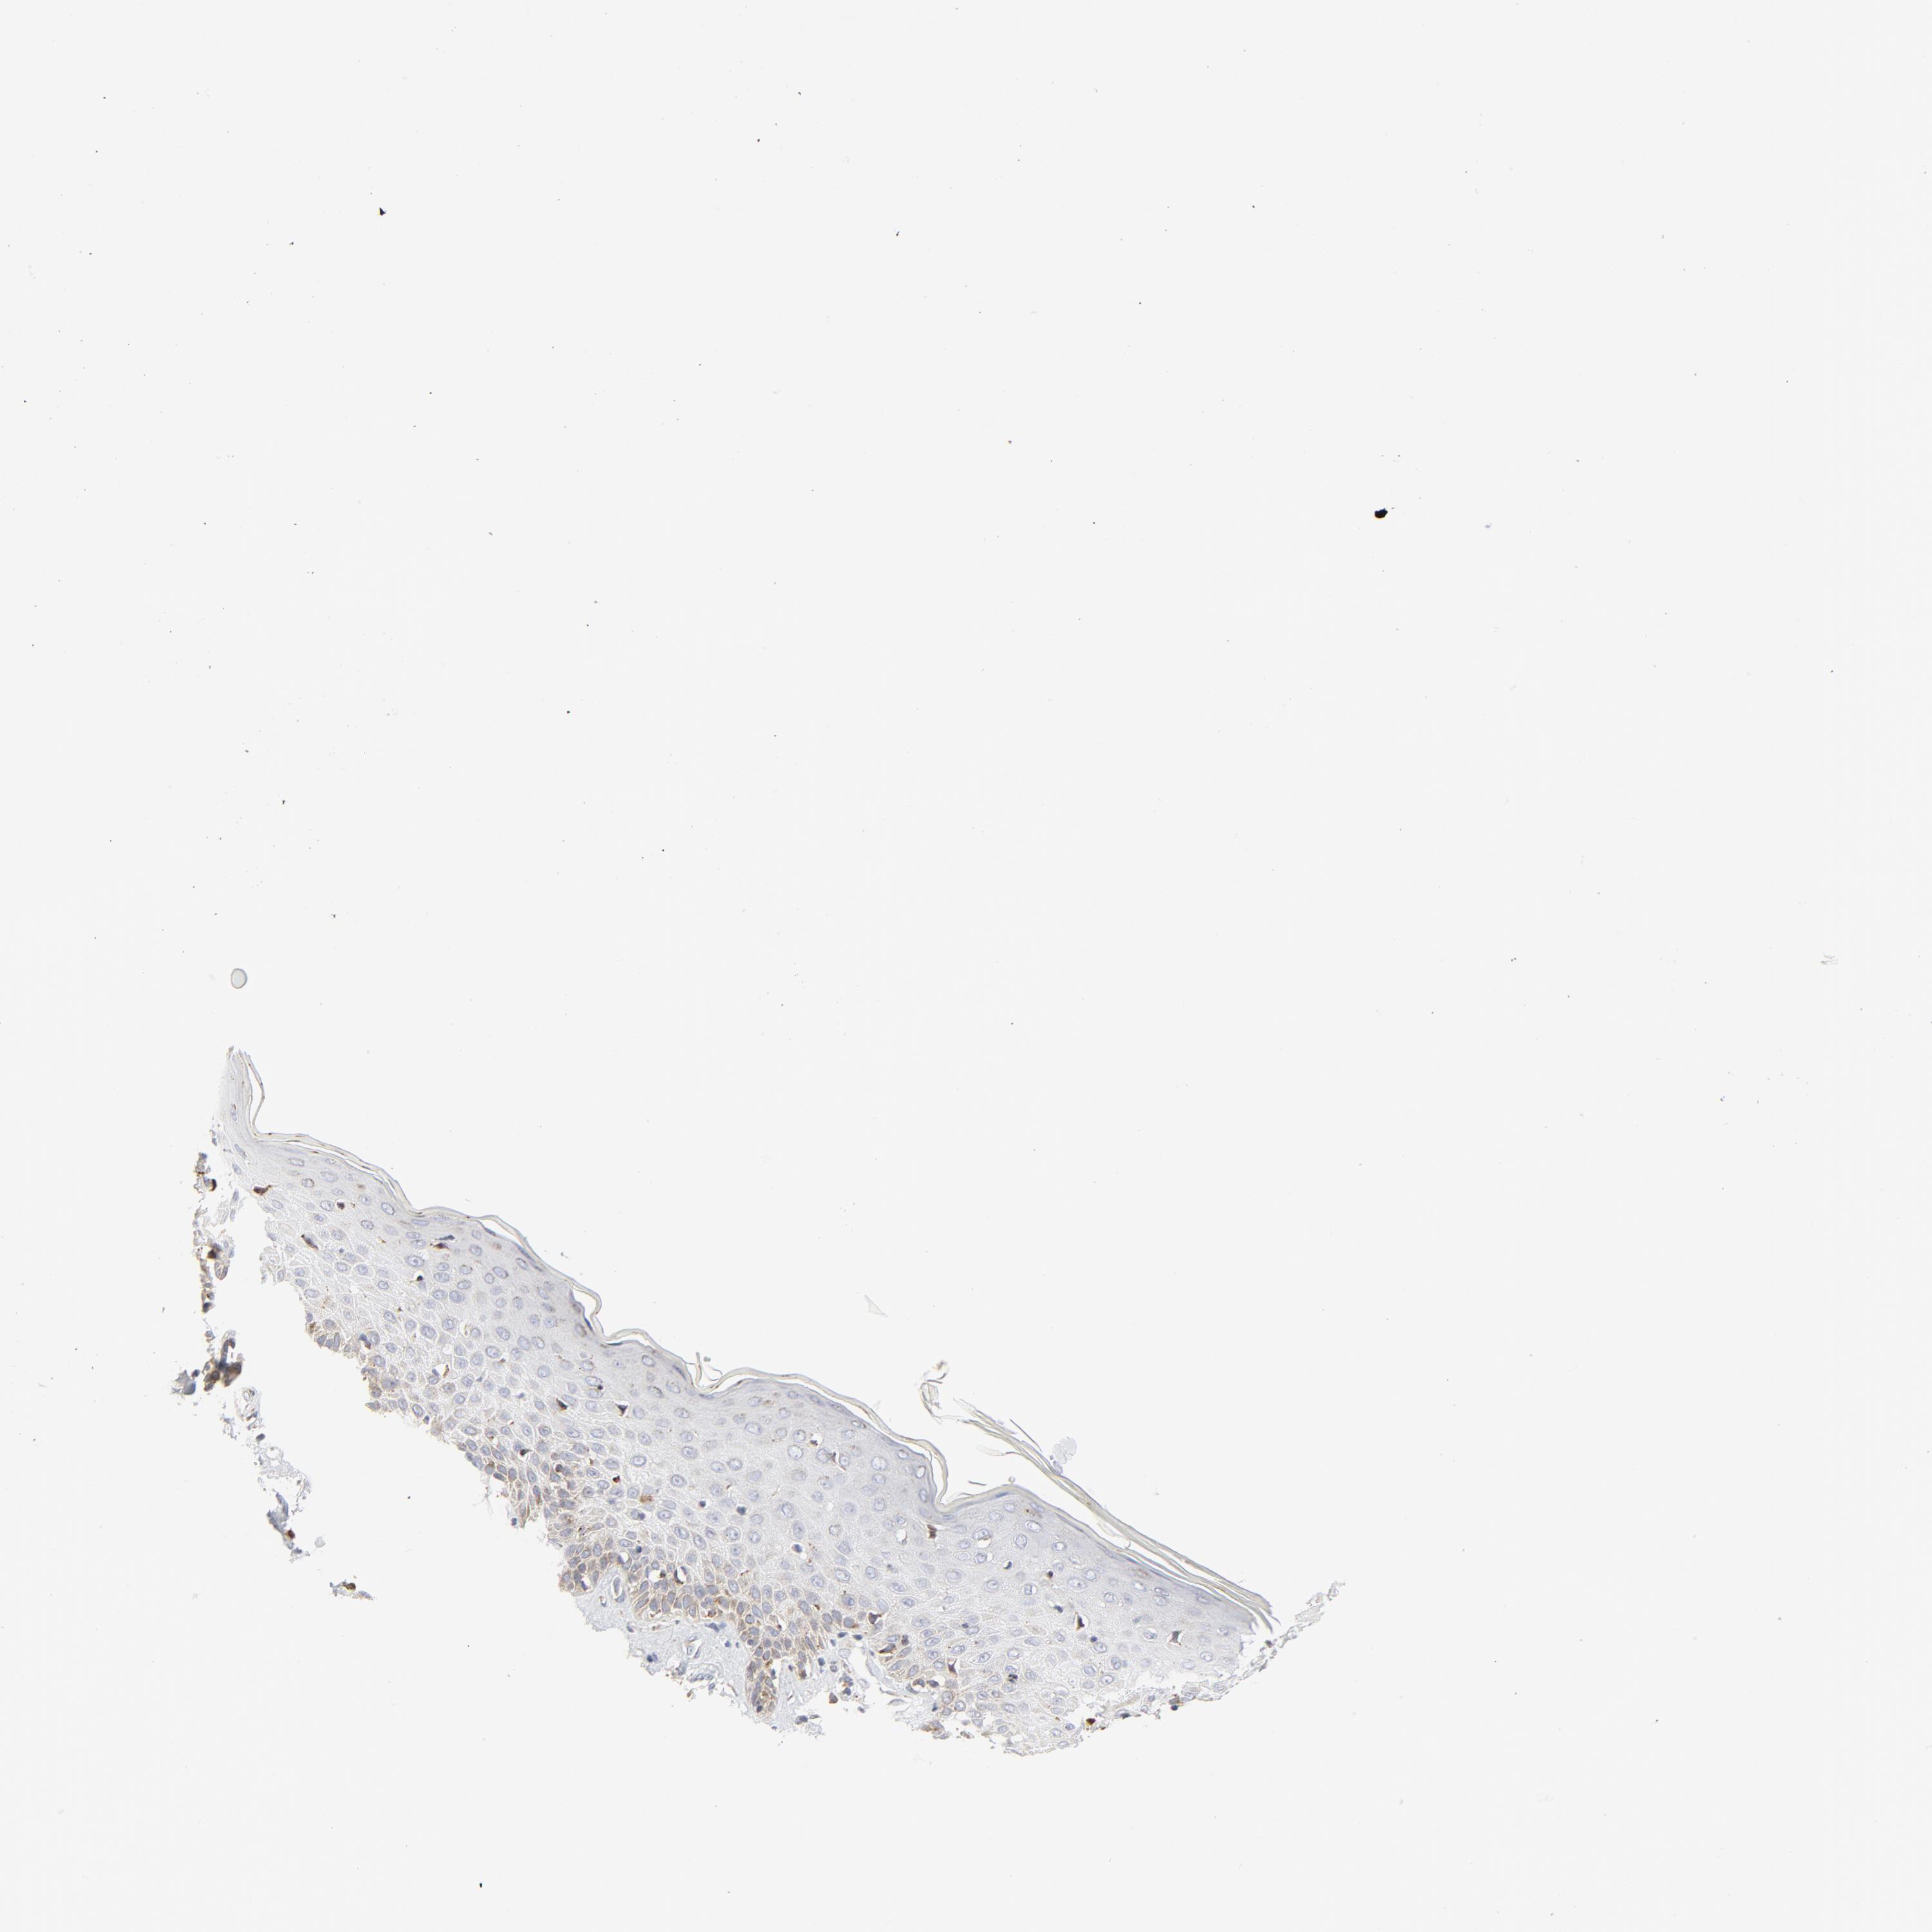

Basal cell and squamous cell cancer

SKIN CANCER - Protein expressioni

A mouse-over function shows sample information and annotation data. Click on an image to view it in a full screen mode. Samples can be filtered based on level of antibody staining by selecting one or several of the following categories: high, medium, low and not detected. The assay and annotation is described here.

Antibody stainingi

Antibody staining in the annotated cell types in the current human tissue is reported as not detected, low, medium, or high, based on conventional immunohistochemistry profiling in selected tissues. This score is based on the combination of the staining intensity and fraction of stained cells.

Each image is clickable and will lead to virtual microscopy that enables deeper exploration of all samples and also displays staining intensity scores, fraction scores and subcellular localization as well as patient and tissue information for each sample.

Squamous cell carcinoma, NOS

Squamous cell carcinoma, metastatic, NOS